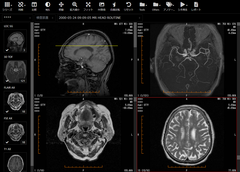

ビューア画面1

ビューア画面1

3. Webブラウザで動作する高速なビューア

ビューアはWebブラウザ(Google ChromeやFirefox)上で動作するので、クライアント端末に新たにソフトウェアをインストールする必要がありません。ネットワーク内のどの端末からでも、WebブラウザからURLにアクセスしてログインするだけで画像を閲覧できます。CTやPETなどの大量の画像が含まれる検査もスピーディに表示することができます。